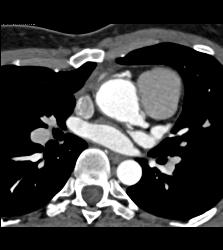

Dilated RCA After Reimplantation S/p Root Repair